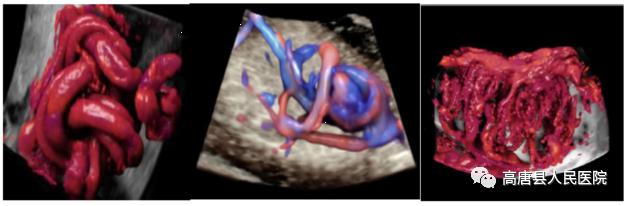

基于全新煊光平台强大的数据处理能力与效率,GE得以将原Voluson 平台上的HDlive技术与HD Flow技术相结合,不仅得到了三维血管栩栩如生的显示,更是在微小血管成像上更加敏锐、可靠。该技术对于深部小血管的立体结构显示极具优势,在评估血管分布或灌注状态时,如同采用血管造影模式。

梦想系列煊光E8先进的探头技术、高品质的基础图像、以及一整套先进的胎儿心脏成像技术来评估胎儿心脏结构和功能,基于革命性的腔内探头技术,将早孕期胎儿心脏检查带入前所未有的水平,分析方法和流程包括:高级STIC (时间空间相关成像) 包括SonoVCAD heart新优势 (胎儿心脏计算机辅助诊断)和STIC M型技术,高级STIC结合B-Flow成像,Z-Score 评价胎儿心脏结构生长的定量工具,包括评估先天性胎儿心脏异常的定量分析,用于高质量的胎儿心脏专项检查。